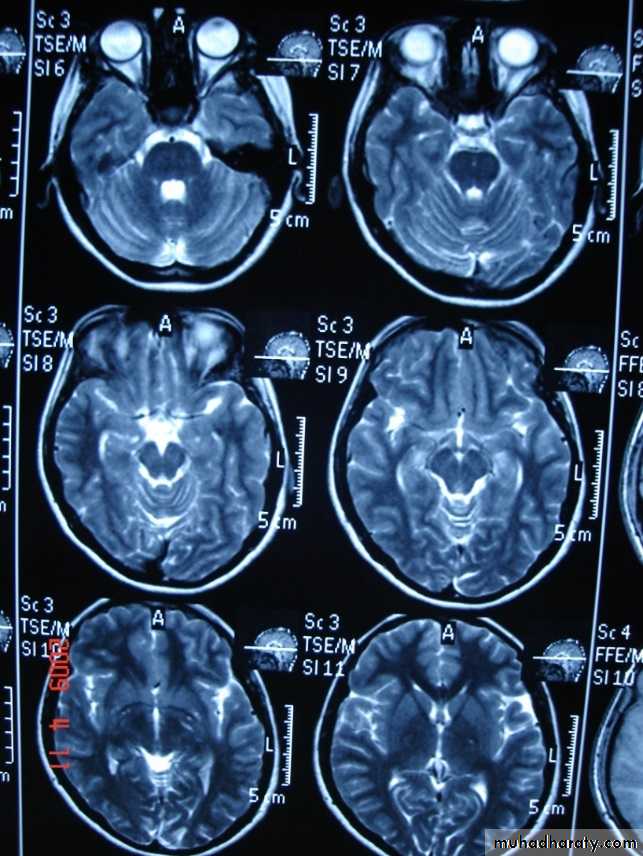

Axial T2-weighted MRI image through the midbrain, showing a right middle cranial fossa homogeneous lesion) with CSF signal intensity and no perceptible wall or internal complexity. There is associated remodeling of the adjacent sphenoid bone and brain displacement..